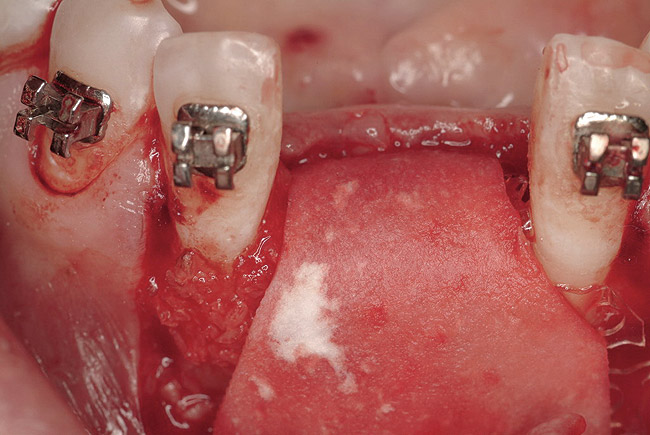

Figure 3  Pre-extraction situation. Tooth Nos. 24 and 25 were planned for extraction, and simultaneous ridge augmentation was planned. Implant placement in these two positions at the conclusion of active tooth movement was also planned.

Figure 3

Figure 6  Following extractions, it was possible to visualize the facial and lingual bony walls.

Figure 6